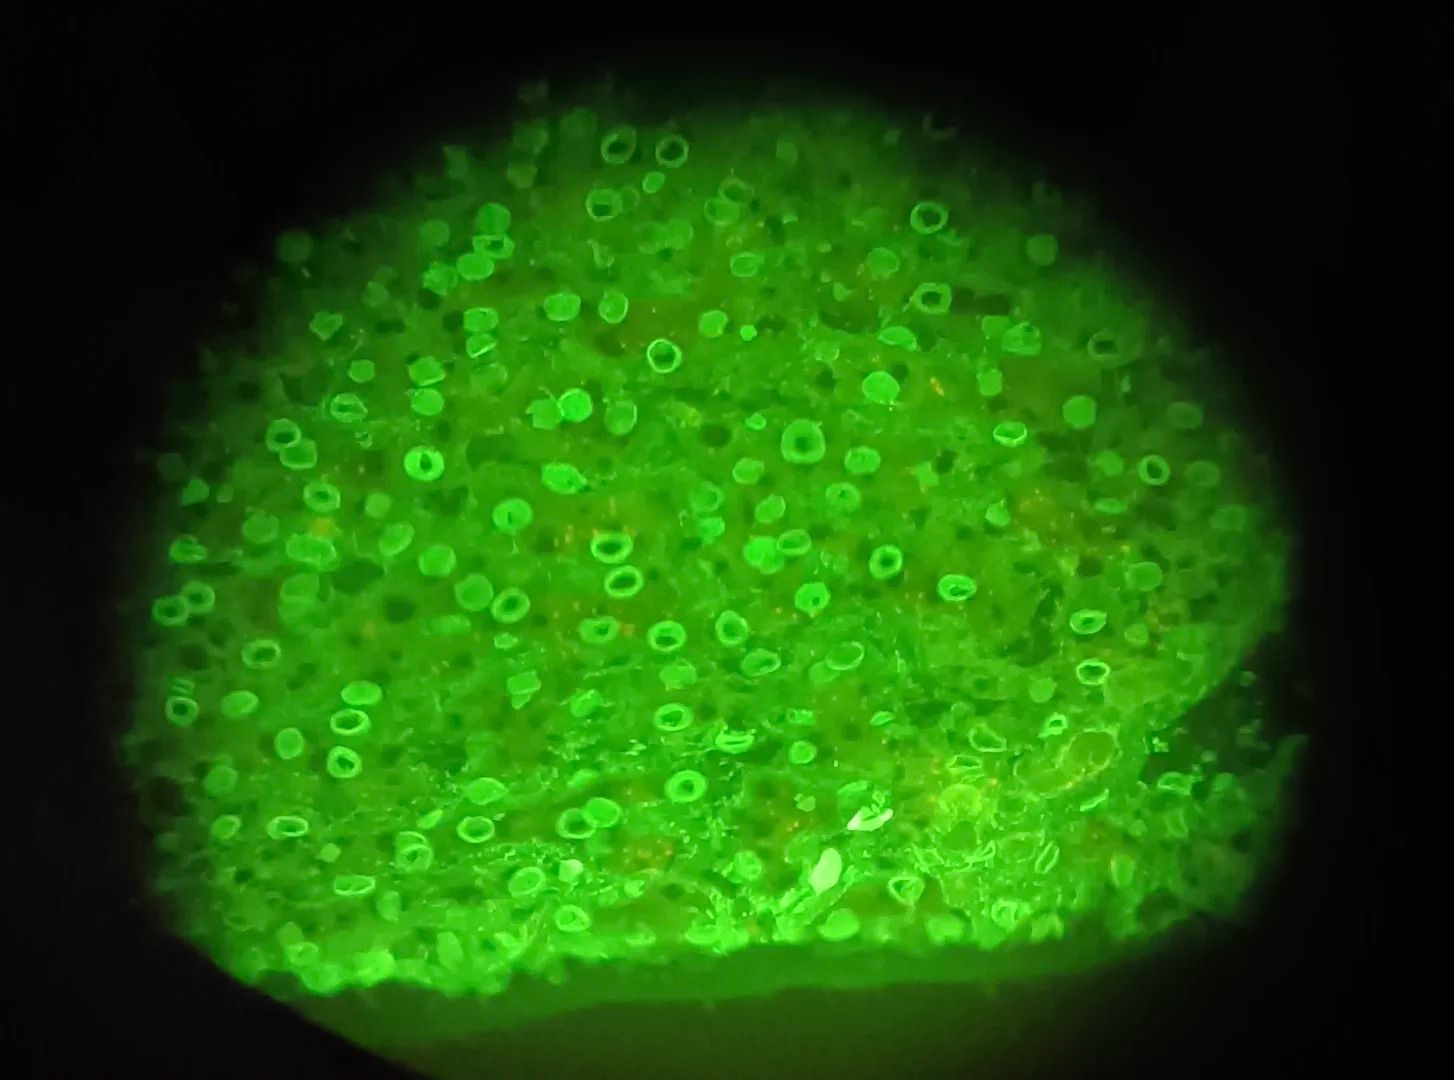

ANA核膜型

ANA著絲點(diǎn)型